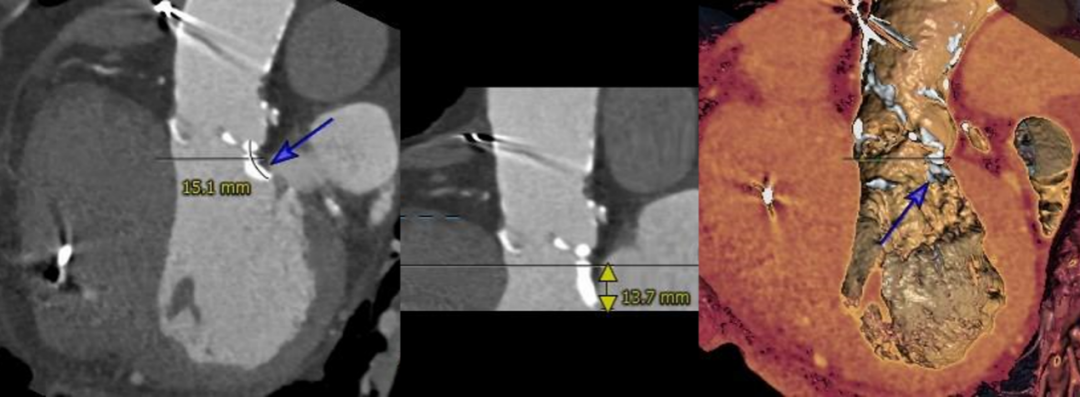

主动脉根部测量

CT特点:三叶式主动脉瓣,瓣叶重度钙化,钙化分布稍欠均匀,主要分布在瓣叶边缘及管壁附着缘,左冠瓣叶窦底长钙化延伸至LVOT;瓦氏窦不大,窦管交界、升主动脉内径偏小,左右冠脉开口高度可,左冠瓣叶稍长,冠脉多发钙化;升主、主动脉弓管壁多发钙化,双侧股髂动脉轻度扭曲,多发钙化,腹主动脉及髂动脉可见瘤样扩张。

瓣上测量

瓣上测量:瓣叶重度钙化,钙化分布稍欠均匀,钙化主要分布在瓣叶边缘,锚定力量主要来源于瓣上2-8mm。

LVOT长钙化

左冠瓣叶窦底长钙化延申至LVOT ,瓣膜锚定难度增高,人工瓣膜存在向下位移风险,增加瓣周漏风险。